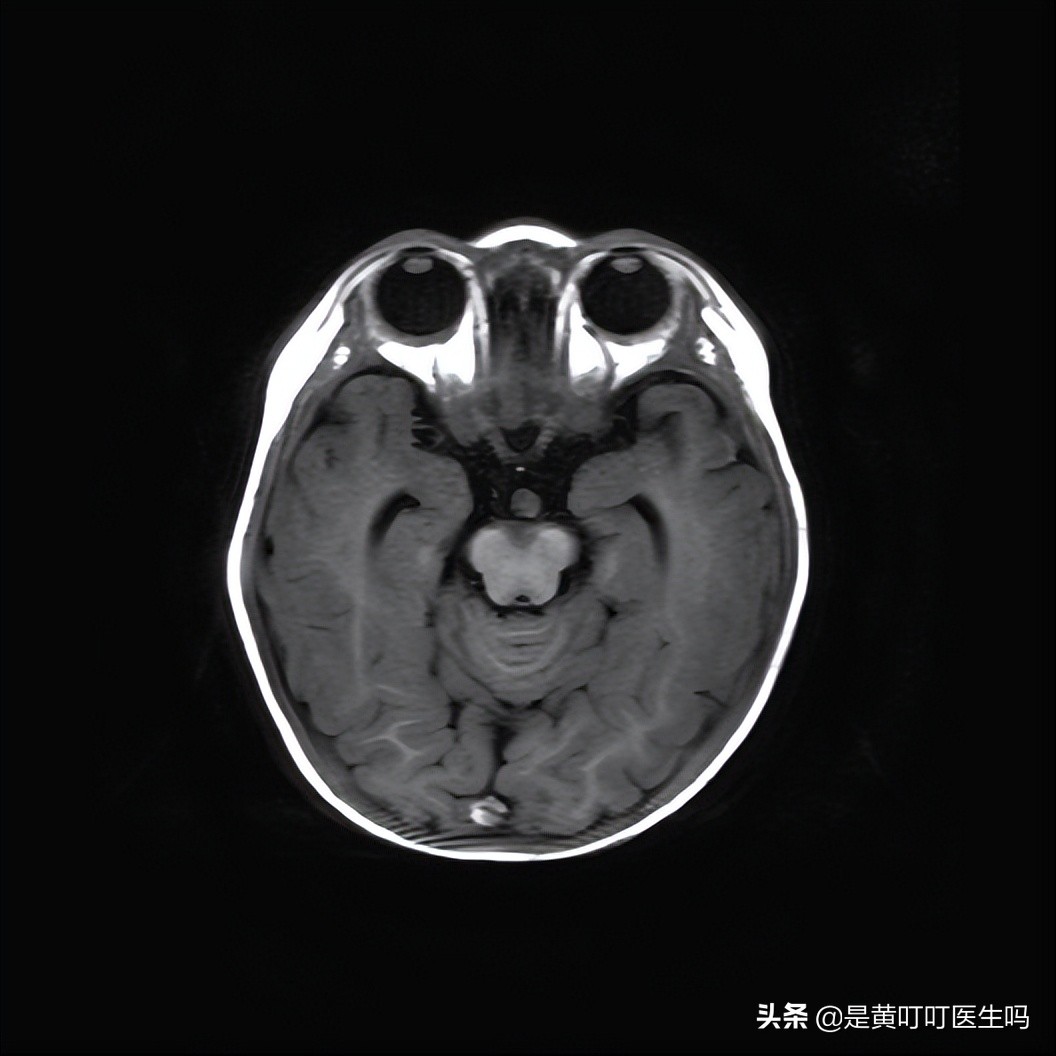

2、颅脑?无需多言,这是人体最重要的中枢,人体所有的行动都靠脑袋指挥。脑袋里面发生了病变,也有可能影响生长发育,导致性早熟。

宝宝的病变很特殊,没经验的放射科医生也许会漏掉病变。

如果有年轻的同行看到这篇文章,不妨先看看病变在哪里。

病变在哪里?